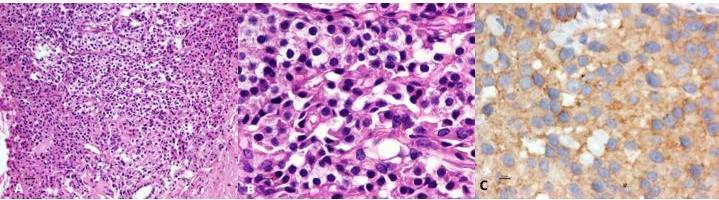

Se realiza gamagrafía con 99mTc-HYNIC-Octreotido y SPECT-CT de abdomen superior que mostró sobreexpresión de receptores de somatostatina en todo el parénquima pancreático, compatible con tumor neuroendócrino (Fig. 3). La endoscopía documentó várices fúndicas GOV 1 de Sarin y cambios por aplicación de cianocrilato y esclerosante en fondo y cuerpo gástrico. Por ultrasonido endoscópico se toman biopsias de cabeza, cuerpo y cola pancreática con diagnóstico de infiltración generalizada del páncreas por tumor neuroendócrino bien diferenciado, G1, Cromogranina (+), sinaptofisina (+) y Ki67<1%. Niveles de insulina, somatostatina y VIP negativos (Fig. 4).